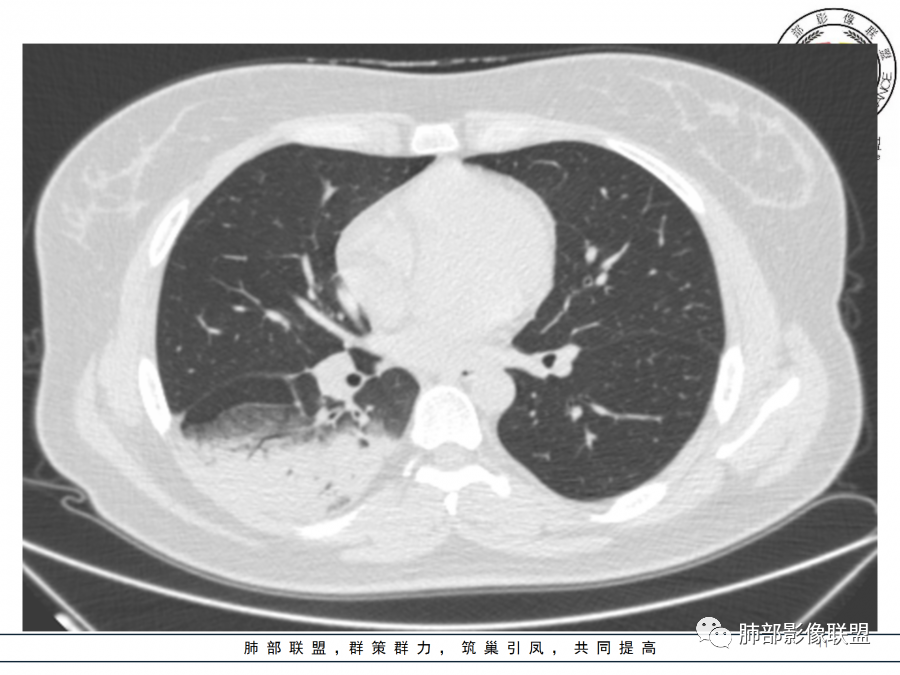

这个病变也不是一个起源中心,胸膜下,多发结节状、实变影。而大叶性肺炎多数由内-外大片状。所以是肺实质多发融合病变。单纯从影像上,还是比较符合隐球菌特点,胸膜下,多发、多中心,相互融合(兄弟齐心)。

你看实性部分,有很多小结节的实性部分,分布很散,不是一个区域,不是按一个段过来的,是多个段,但是内基底段似乎又不受累。所以大叶性肺炎,一般细菌性的这个影像特点还是不太支持。

隐球菌,胸膜下病灶,多个起源中心,最终还是融合在一起,侧向融合为主的。

隐球菌,侧向融合、外围胸膜下为主,也有累及叶段的、比较少。

1.年轻女性,咳嗽、发热(38.8°),起病急,血象高。影像上大片实变影为主,一般会首先考虑细菌性肺炎,尤其是肺炎链球菌感染等。疗效不满意时考虑其他。

2.影像上怀疑其他病灶的理由有:

1)实变影为大小不等多中心性。

2)沿胸膜下分布趋势(不同于大叶性肺炎的肺叶“造型”)。

3)周围较大范围磨玻璃影及小叶间隔增厚。

4)病灶体积增大明显(叶间裂推移)。

3.腺病毒肺炎可以符合上述改变:实性密度,间质分布为主等。

4.隐球菌感染可以符合上述改变:胸膜下多中心实变密度为主,磨玻璃晕等。但隐球菌临床症状大多隐匿、迁延,影像变化缓慢。

5.本例患者血象高,影像渗出明显,尚不能排除混合感染可能。